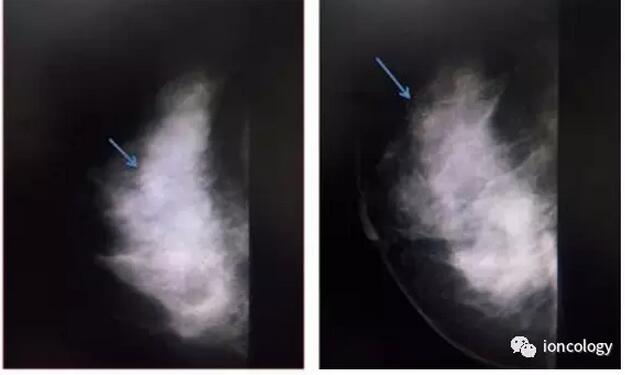

钼靶示:右侧乳腺外上象限可见肿块,其内可见成簇钙化灶,范围约14.2 mm×15.8 mm,BI-RADS 4C 类。